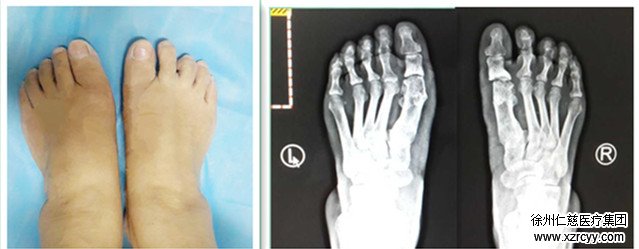

拇外翻畸形术后外观 拇外翻畸形术后X线片

一个多月前,betway在线登陆为张女士成功开展了微创小切口拇外翻的截骨矫形术,折磨了老年人近30年的拇外翻终于去除了,而复查结果显示张女士手术恢复非常好。张女士开心的说,在必威官方首页官网betway不光治好了她的拇外翻,还能使用医保,省了不少钱。

“手术在腰麻或局部麻醉下完成,术中透视达到满意位置后方关闭伤口,保证了手术质量。”曹主任介绍,由于采用了内固定,术后即可下地行走,大大方便了病人。而且新的手术方式使病人痛苦更小,足部切口小,创伤小,疗效更确切,恢复更快,并发症更少,是目前治疗拇外翻的理想方法,得到了广大患者的肯定。